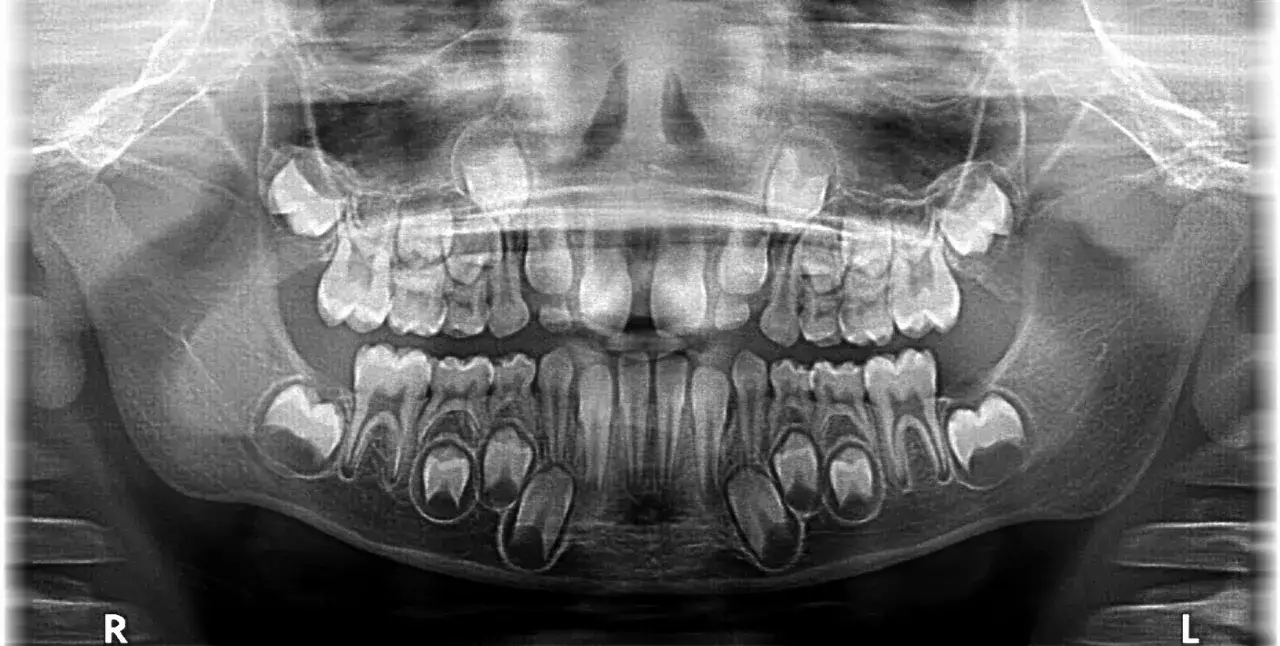

W stomatologii, zwłaszcza w Polsce, do oznaczania zębów używamy międzynarodowego systemu FDI (Federation Dentaire Internationale). System ten przypisuje każdemu zębowi dwucyfrowy numer, gdzie pierwsza cyfra oznacza kwadrant jamy ustnej, a druga pozycję zęba w tym kwadrancie. I tu właśnie pojawia się niejednoznaczność, która często wprowadza rodziców w błąd.

Dla zębów mlecznych, kwadranty oznaczane są cyframi od 5 do 8. Kwadrant 5 to górny prawy, 6 – górny lewy, 7 – dolny lewy, a 8 – dolny prawy. Pozycje zębów w każdym kwadrancie liczy się od 1 do 5, zaczynając od siekaczy, przez kły, aż do trzonowców. Oznacza to, że mleczne „piątki” to tak naprawdę drugie trzonowce mleczne. Przykładowo, ząb oznaczony jako „55” to górny prawy drugi trzonowiec mleczny, a „75” to dolny lewy drugi trzonowiec mleczny. Są to zęby, które pojawiają się w jamie ustnej dziecka stosunkowo późno w uzębieniu mlecznym.

Jednak w mowie potocznej, kiedy rodzice mówią o „piątkach”, najczęściej mają na myśli stałe drugie przedtrzonowce. Te zęby pojawiają się w uzębieniu mieszanym, czyli w okresie, gdy dziecko ma zarówno zęby mleczne, jak i stałe. W systemie FDI stałe drugie przedtrzonowce oznaczane są jako 15, 25, 35, 45, w zależności od kwadrantu. Warto zapamiętać to rozróżnienie, ponieważ mleczne drugie trzonowce i stałe drugie przedtrzonowce to zupełnie inne zęby, wyrzynające się w różnym czasie i pełniące nieco inne funkcje, choć oba są kluczowe dla prawidłowego żucia.

W przypadku mlecznych „piątek”, czyli drugich trzonowców mlecznych, ich wyrzynanie następuje zazwyczaj między 23. a 33. miesiącem życia dziecka. Oznacza to, że uzębienie mleczne, składające się z 20 zębów, jest zazwyczaj kompletne do około 2-3 roku życia. To właśnie te zęby, wraz z pierwszymi trzonowcami mlecznymi, odgrywają kluczową rolę w rozdrabnianiu pokarmu w najmłodszych latach życia.

Natomiast stałe „piątki”, czyli drugie przedtrzonowce stałe, pojawiają się znacznie później. Ich wyrzynanie ma miejsce zazwyczaj około 10-12 roku życia. Wyrzynają się one w miejscu, gdzie wcześniej znajdowały się mleczne drugie trzonowce (czyli te, które w systemie FDI były "piątkami" mlecznymi). Jest to etap uzębienia mieszanego, kiedy w jamie ustnej dziecka współistnieją zęby mleczne i stałe.

Ogólna kolejność wymiany zębów mlecznych na stałe rozpoczyna się około 5-6 roku życia, zazwyczaj od pierwszych stałych trzonowców (szóstek) oraz siekaczy, i trwa aż do około 12-13 roku życia. Warto pamiętać, że tempo wyrzynania zębów może się różnić u poszczególnych dzieci. Chociaż istnieją pewne normy, niewielkie odchylenia są często naturalne. Jeśli jednak zauważą Państwo znaczne opóźnienia lub inne niepokojące objawy, zawsze warto skonsultować się ze stomatologiem dziecięcym. Z mojego doświadczenia wiem, że wczesna konsultacja może zapobiec wielu problemom ortodontycznym w przyszłości.